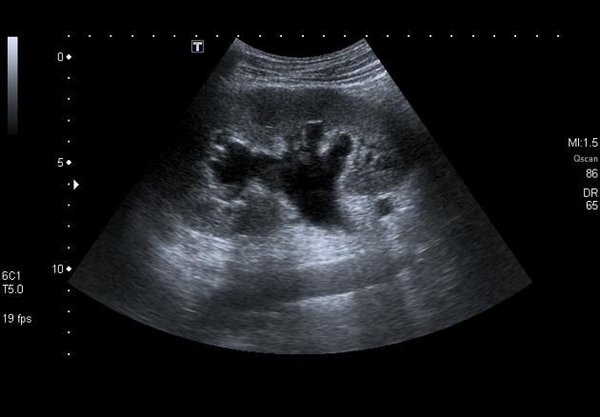

#Асцит – патологическое состояние, при котором в ️брюшной полости (животе) начинает скапливаться жидкость. Самой частой причиной является #цирроз печени (до 90% всех выявляемых асцитов), вторым по частоте #онкологический асцит.

‼️Для диагностики необходим осмотр врача и #ультразвуковое исследование. ️Симптомы асцита:

-Увеличение живота в объеме; -Одышка; -Реже — боль (за счет растяжения брюшной стенки).

Что показывает УЗИ при асците:

Подтверждает факт наличия свободной жидкости.

Оп… — Читать дальше

Находит причину — часто видит изменения в печени, почках, поджелудочной железе, опухоли.

Контролирует лечение — помогает отслеживать, уходит ли жидкость.

Безопасно и направляет — без боли и излучения, а главное — показывает врачу, куда двигаться дальше для вашего эффективного лечения.

Не стоит гадать и ждать. Своевременная диагностика — это ключ к правильной тактике лечения и улучшению качества жизни ️